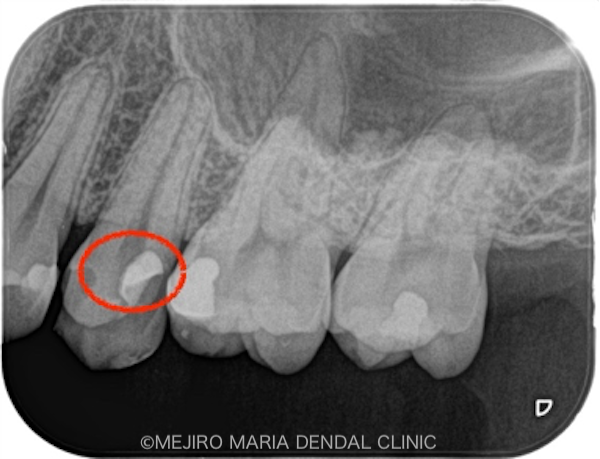

による歯髄保存症例(精密根管治療)_レントゲン_治療前2.png)

赤丸は近接しているう蝕(虫歯)箇所

患者様は、他院にて虫歯治療をおこなった際に、「虫歯が深くまで進行しており、神経の処置(根管治療)が必要です」と説明を受け、当院へ来院されました。虫歯の治療箇所には、治療前には痛みや違和感はなく、患者様は「なぜ神経の治療が必要なのか?」と疑問に思われていました。

当院での診査の結果、前の歯科医院で処置をした後だったために、正確な診断までには至りませんでしたが、「可逆性歯髄炎」と診断し、この歯の神経は保存できると判断しました。